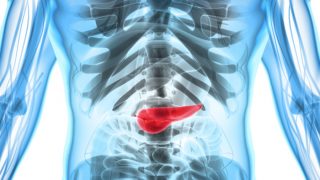

有几个有用的家庭疗法来治疗胰腺炎,包括使用针灸,豆腐,红葡萄,灵芝,酸奶,菠菜,人参和蓝莓的,与某些生活方式的改变一起。胰腺炎是胰腺的炎症,小腺体,附近存在腹腔的顶部。当腺体发炎,周围的血管也可以得到发炎,并有可能是出血和感染。随着时间的推移,胰腺开始